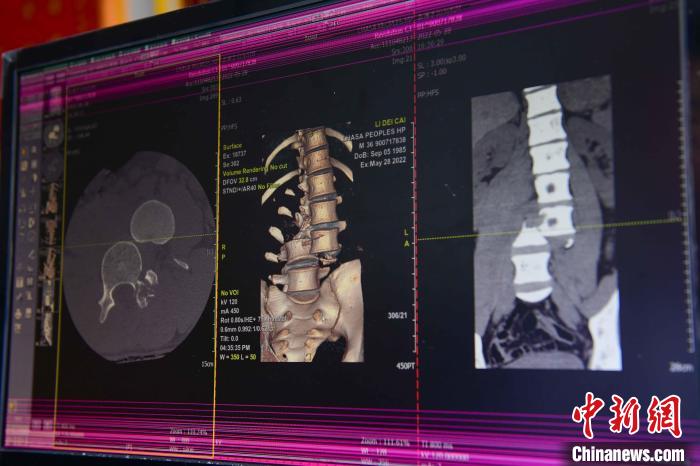

圖為患者術前,腰3/4脊柱骨折伴脫位?!≡髑?攝

通道開通后,拉薩市人民醫(yī)院完成了兩例脊柱創(chuàng)傷截癱患者的救治。一例23歲的病患為胸12椎體爆裂骨折伴截癱,另一例36歲的病患腰椎體骨折脫位伴雙下肢癱。按照脊髓損傷救治綠色通道流程,術前充分快速完善相關檢查,充分術前評估,向患者詳細交代手術風險,入院當天急診行手術治療。

北京“組團式”醫(yī)療援藏專家、主治醫(yī)師何蔚介紹,兩名患者屬于脊柱骨折合并雙下肢截癱,手術十分復雜,需要快速且安全的完成手術,在脊柱外科手術中屬于四級手術,難度最高的一種。